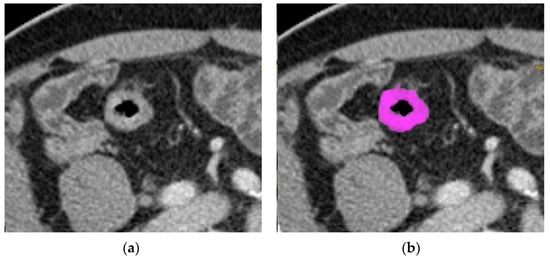

2.3. Texture Analysis